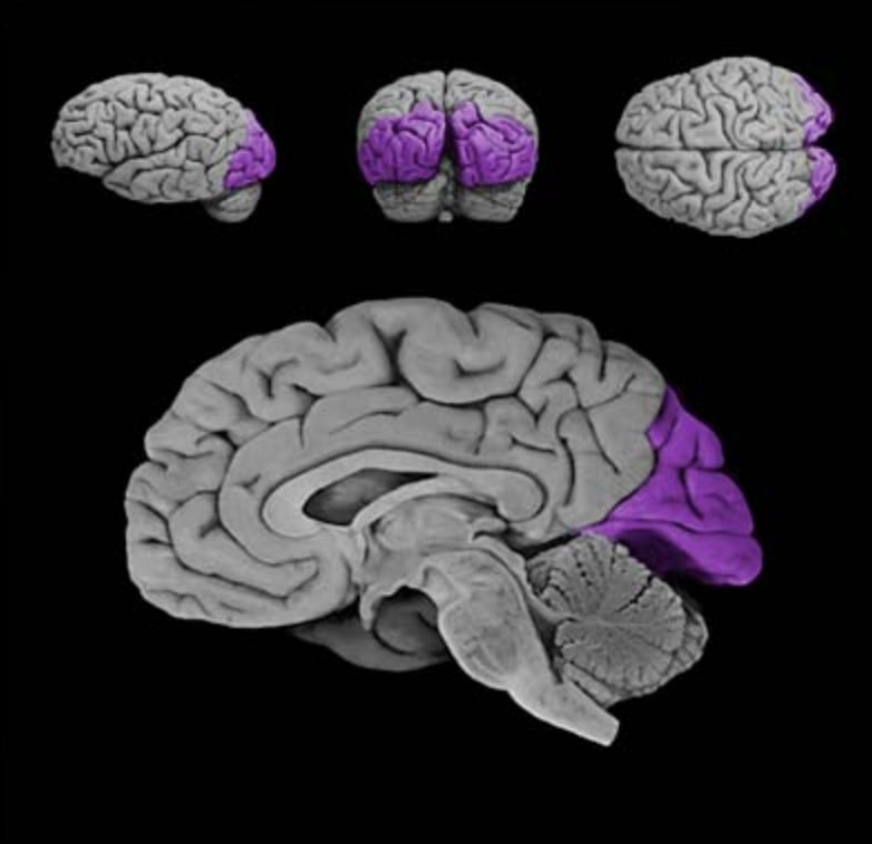

Brodmann's area 17

Sensory cortical area in the banks of the calcarine sulcus (lingual and cuneus gyral formations of the medial occipital lobe); this area corresponds to the primary visual cortex (also known as "striate cortex").

Calcarine sulcus

A prominent sulcus in the medial occipital lobe formed by the cuneus and lingual gyral structures; this sulcus extends roughly horizontally from the parieto-occipital sulcus to its termination in the occipital pole. The calcarine sulcus contains the primary visual cortex (also called the "striate cortex").

Primary visual cortex

Cortical area (Brodmann's area 17; also referred to as the "striate cortex") in the banks of the calcarine sulcus that first receives visual signals from the relevant thalamic nucleus (lateral geniculate nucleus).